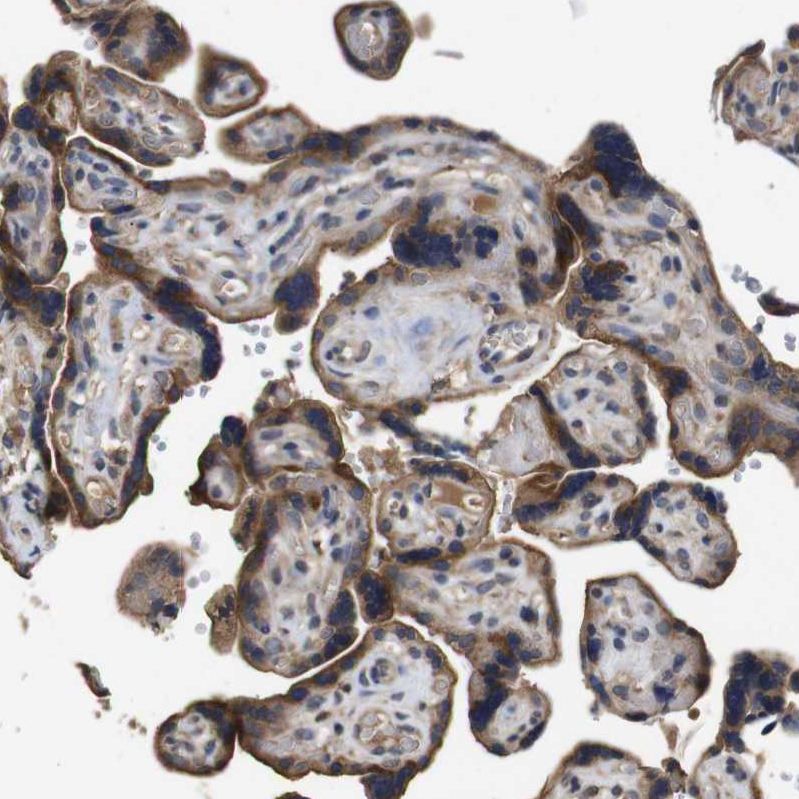

Immunohistochemical staining of human kidney shows strong cytoplasmic and membranous positivity in cells in tubules.